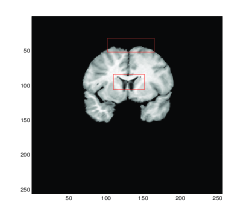

5.2 Test 2: A Pair of Brain MR Images

We take as Test 2 a pair of medical images of size 256×256256256256\times 256 from the Internet Brain Segmentation Repository (IBSR) http://www.cma.mgh.harvard.edu/ibsr where 20 normal MR brain images and their manual segmentations are provided. We choose the particular pair of individuals with different sizes of ventricle to illustrate a large deformation problem. Figure 3 shows the test images and the registration results using Gaussian curvature model. We can see that the model is able to solve real medical problems involving large deformations, which is particularly important for atlas construction in medical applications.

Figure 4 shows the transformed template images for all four methods. We can see that Gaussian curvature gives the best result inside the red boxes in comparison with the diffeomorphic demon, the linear and mean curvature models as depicted in Figure 4 (d).

Refer to caption

(a) Model D

(b) Model LC

(c) Model MC

(d) Gaussian curvature

Figure 4: Test 2: A pair of Brain MR images. Comparison of Gaussian curvature with competing methods. The transformed template image using (a) Model D, (b) Model LC, (c) Model MC, and (d) Gaussian curvature. Notice the differences of these three images inside the red boxes. Considerably more accurate results are obtained, particularly within these significant regions, by employment of the Gaussian curvature model.